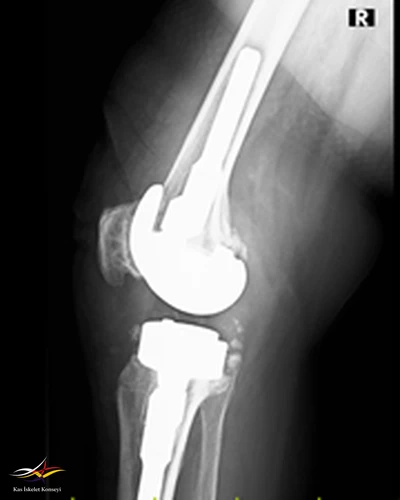

Hikaye: Dört yıl önce sağ dize total protezi uygulanan hastanın üç ay önce ortopedi kliniğine aynı dizde ağrı ve eklemde kısıtlılık ile başvurduğu ve mevcut protezin revize edilmesi kararı verildiği öğrenildi. Başvurmasından iki ay önce revizyon diz protezi yapılıyor. Ameliyattan sonra düşük ayak gelişiyor. Ev egzersizleri, ortez ve multivitamin ile taburcu ediliyor.

Muayene: Sağ ayak dorsifleksiyon kas gücü 0/5, diğer kas güçleri tam. Sağ diz EHA fleksiyon aktif 100 dereceye kadar ağrısız, ekstansiyon tam. Pasif EHA 110 derece ağrısız.